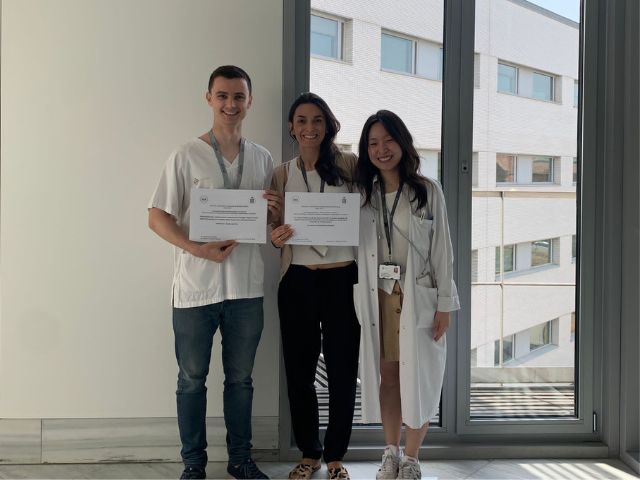

23/11/2023Investigacions del Servei de Reumatologia, reconegudes amb beques de prestigi nacional i estatal

Cada any, la Societat Catalana de Reumatologia atorga beques amb el seu nom amb l’objectiu d’impulsar el desenvolupament i la recerca en el camp de la Reumatologia a Catalunya. Enguany, dues d’aquestes beques han estat atorgades a treballs d’investigació dels professionals del Servei de Reumatologia de l’Hospital de Sant Pau, i una tercera per part la Sociedad Española de Reumatología. -